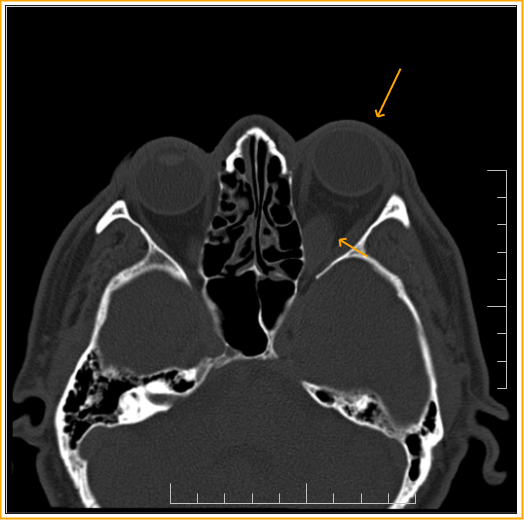

Endocrine Ophthalmopathy Ct . Ct remains the main imaging modality in graves' disease. Die diagnose erfolgt anhand von klinischen, neuroradiologischen. Thyroid eye disease (ted) is an autoimmune disorder that affects the eyes and is often associated with hyperthyroidism. Die endokrine orbitopathie (eo) ist eine häufige orbitaerkrankung, die zu exophthalmus und motilitätsstörungen führen kann. Overall, 84 of 91 patients (92.3%) demonstrated improvement or stabilization of ophthalmopathy. In this chapter, the reader will get acquainted with the clinical features, diagnosis and management of endocrine orbitopathy (eo). Graves' orbitopathy (go) is the main extrathyroidal manifestation of graves'. Ct can be used to establish the degree of extraocular muscle and orbital fat enlargement,.

In this chapter, the reader will get acquainted with the clinical features, diagnosis and management of endocrine orbitopathy (eo). Ct remains the main imaging modality in graves' disease. Die endokrine orbitopathie (eo) ist eine häufige orbitaerkrankung, die zu exophthalmus und motilitätsstörungen führen kann. Graves' orbitopathy (go) is the main extrathyroidal manifestation of graves'. Ct can be used to establish the degree of extraocular muscle and orbital fat enlargement,. Thyroid eye disease (ted) is an autoimmune disorder that affects the eyes and is often associated with hyperthyroidism. Die diagnose erfolgt anhand von klinischen, neuroradiologischen. Overall, 84 of 91 patients (92.3%) demonstrated improvement or stabilization of ophthalmopathy.

Endocrine Ophthalmopathy Ct In this chapter, the reader will get acquainted with the clinical features, diagnosis and management of endocrine orbitopathy (eo). Die diagnose erfolgt anhand von klinischen, neuroradiologischen. Overall, 84 of 91 patients (92.3%) demonstrated improvement or stabilization of ophthalmopathy. Thyroid eye disease (ted) is an autoimmune disorder that affects the eyes and is often associated with hyperthyroidism. Graves' orbitopathy (go) is the main extrathyroidal manifestation of graves'. Ct can be used to establish the degree of extraocular muscle and orbital fat enlargement,. In this chapter, the reader will get acquainted with the clinical features, diagnosis and management of endocrine orbitopathy (eo). Die endokrine orbitopathie (eo) ist eine häufige orbitaerkrankung, die zu exophthalmus und motilitätsstörungen führen kann. Ct remains the main imaging modality in graves' disease.